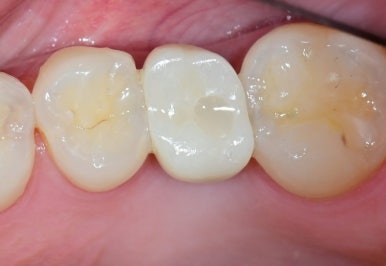

📸 치료 후 Before & After

- 보철물 형태가 자연스러운 곡선으로 회복

- 잇몸 라인이 매끄럽게 정리됨

- 음식물 끼임 및 이물감 해소

특히, 기존에 각지고 눌려 있던 보철물의 뒷면이

새 보철물에서는 부드럽고 잇몸 친화적인 형태로 바뀌었음을

확인할 수 있었습니다.